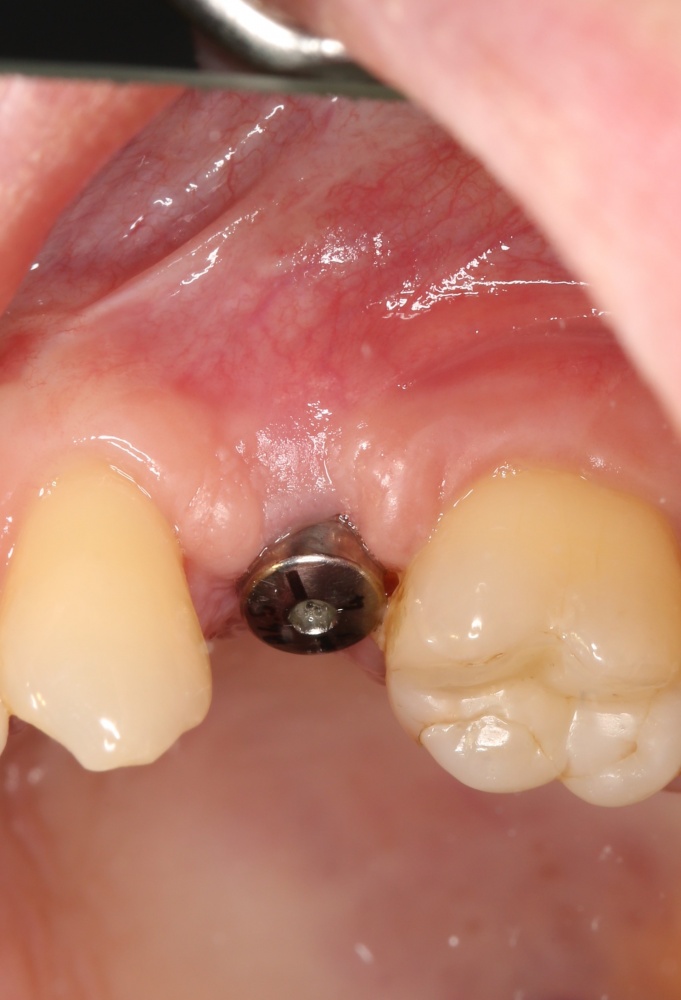

Но, если мы говорим не о поиске истины, а о выборе метода лечения? К примеру, мы столкнулись с распространенной ситуацией:

или вот:

когда атрофия альвеолярного гребня препятствует установке правильных имплантатов в правильное положение (см. Рекомендации по установке имплантов. Часть V).

Теперь возьмём клинический случай (нижняя челюсть, отсутствия 35, 36, 37 зубов, атрофия альвеолярного гребня по ширине):